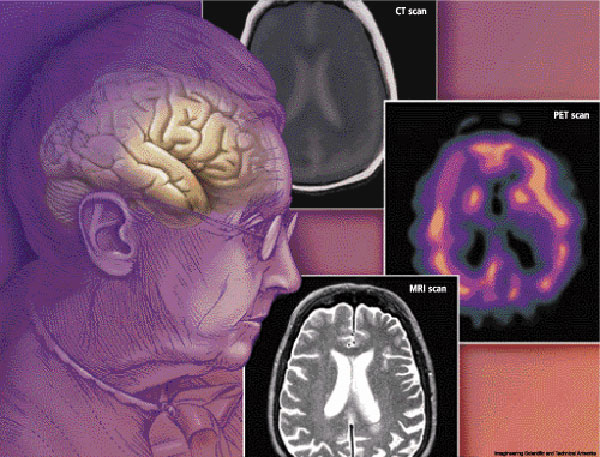

تشخیص زوال عقل یا دیمانسیا

از آنجا که زوال عقل یک اصطلاح کلی است که کاهش عملکرد شناختی را توصیف می کند و در نتیجه انواع مختلفی از زوال عقل را به وجود می آورد، هیچ آزمایشی برای تعیین اینکه فرد به این بیماری مبتلا است وجود ندارد. با توجه به این نکته، پزشک معاینه جسمی کاملی را انجام می دهد که شامل یک شرح حال پزشکی عمیق، آزمایشات آزمایشگاهی و اسکن مغز مانند CT یا MRI نیز می شود تا مشخص کند علائمی که نشان می دهید مربوط به زوال عقل است یا خیر.

بسته به آموزش پزش ، آنها ممکن است ارزیابی های بیشتری را برای تعیین نوع زوال عقل انجام دهند. در غیر این صورت، ممکن است لازم باشد شما را به متخصصی مانند متخصص مغز و اعصاب که می تواند تشخیص دقیق بدهد ارجاع دهند.